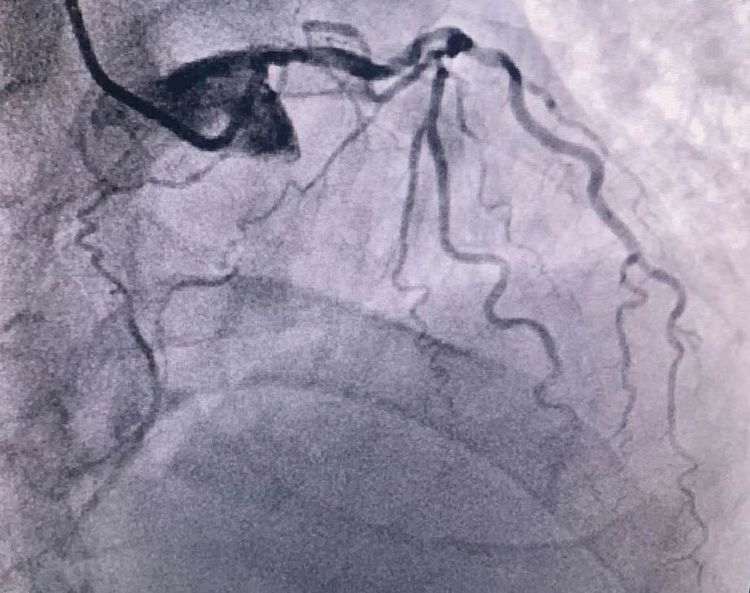

患者前降支、右冠100%閉塞,LCX中段60%狹窄。命懸一線,手術(shù)臺(tái)上持續(xù)胸痛。和患者家屬及時(shí)溝通后,決定行PTCA術(shù)。血壓低至60/40mmHg,在主動(dòng)脈內(nèi)球囊反博的支持下緊急行PCI術(shù)。軌道很快建立,導(dǎo)絲也及時(shí)通過病變血管,噩夢(mèng)來了,患者發(fā)生室顫了。在吳棟梁院長的指揮下,李陽主任和心臟團(tuán)隊(duì)的成員共同努力下,除顫、冠脈內(nèi)溶栓、多個(gè)球囊輪流上陣,患者病情平穩(wěn)了,罪犯血管及時(shí)開通,血流恢復(fù)三級(jí)血流。平安下臺(tái),準(zhǔn)備擇日再處理冠脈情況。